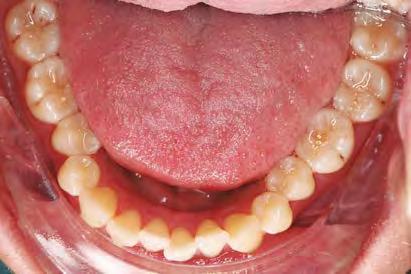

–MARPE, una alternativa a la disyunción en el paciente adulto, por el Dr. Enrique Solano y cols. [88]